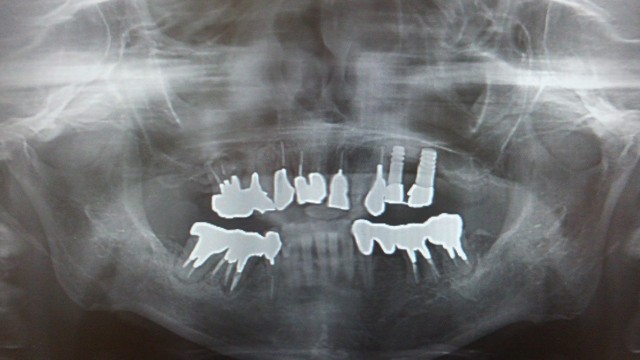

奥のインプラントは完全に抜けています。

手前のインプラントはどうにか骨にくっついています。

手術したその日から、奥のインプラントはグラグラだったそうです。

補償を求めたところ、手前のインプラントとワイヤーで連結されたそうです。

奥のインプラントは歯茎に刺さっています。

上顎洞に骨移植した形跡なんてまるでありません。

抜けているインプラントのせいで、ひどい上顎洞炎(ちくのう症)になっていました。

この上顎洞炎を治すのに二か月間、インプラントを抜いた穴から洗浄を繰り返しました。